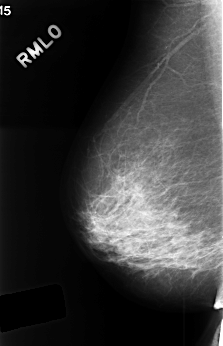

C_0405_1.RIGHT_MLO

RIGHT_MLO LINES 4488 PIXELS_PER_LINE 2888 BITS_PER_PIXEL 12 RESOLUTION 50 NON_OVERLAY